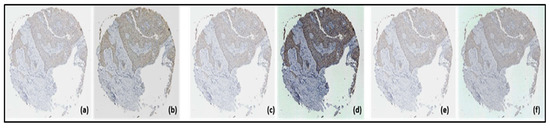

3.4. Segmented Images

3.3.2. Histogram Equalization Imaging Results

3.3.3. Image Results of Histogram Matching